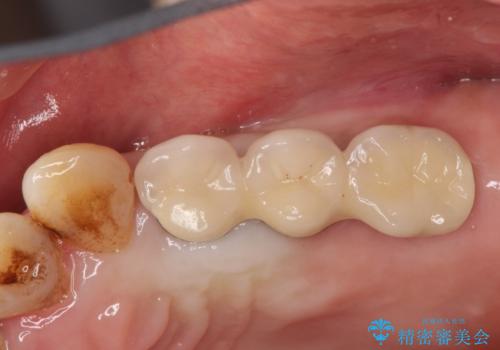

- 奥歯が欠損していることを主訴に来院されました。

インプラントにて補綴治療を行なっております。

綺麗になり、しっかり噛めるようになったと満足していただきました。